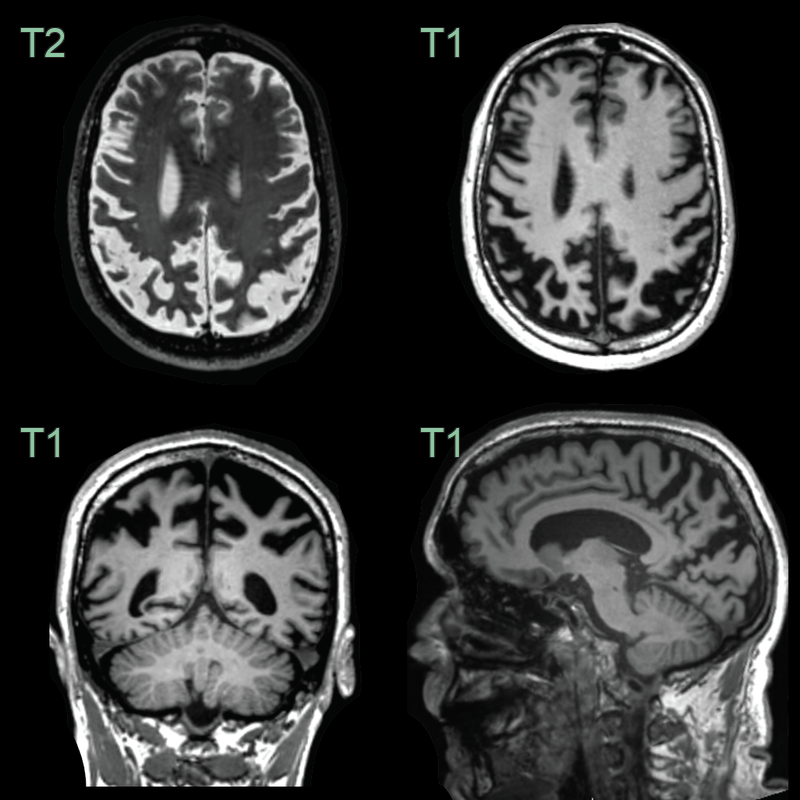

• 70-year-old patient with apraxia, myoclonus and alien limb phenomenon.

• MRI showed severe parietal atrophy but no parenchymal signal abnormality.